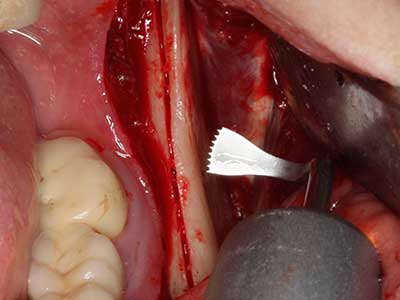

When surgical procedures are performed on bone in the immediate vicinity of sensitive structures such as blood vessels or nerves, rotary instruments pose a significant risk of iatrogenic injury. Piezoelectric devices can be helpful for preparation of bone covers and removal of hard tissue close to nerves, particularly for exposure of nerves after iatrogenic injury but also during nerve lateralization for resective and reconstructive procedures or implant placement (Fig. 17-20). Light contact between the piezotip and the nerve does not generally result in damage but proceeding incautiously with saw-like motions or attachments where a residual bone substrate remains may cause temporary or even permanent nerve damage. However, the risk of damage is considered to be substantially lower than when using saws or milling instruments (Pereira, Gealh et al. 2014).

Fig. 18: Preparation of a cortical cover with the piezo bone saw (Piezomed, W&H).

Fig. 19: Surgical site after neurolysis and removal of osteoma.